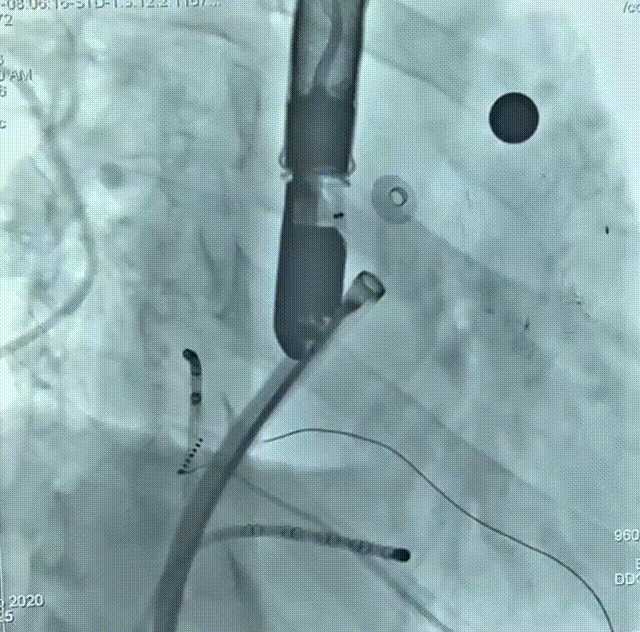

术后造影

患者为51岁男性,因“反复心悸7-8年”入院,有明确的脑梗死病史,近4年内出现2次脑梗死,右侧肢体存在活动障碍后遗症,考虑由房颤相关血栓栓塞造成。术前动态心电图示心律不齐,房颤律,心脏彩超示左右房内径增大、左室收缩功能减低;房颤CHA₂DS₂-VASc评分4分、HAS-BLED评分4分,血栓栓塞及出血风险均较高;食道超声联合CT重建示左房及心耳内未见明显血栓形成,左心耳偏大。结合评估结果和患者及家属意愿,拟使用我国自主研发的Bio-Lefort生物可降解左心耳封堵器,行导管消融+左心耳封堵“一站式”手术。射频消融完成后实施左心耳封堵,术中牵拉试验提示封堵器稳定,符合释放原则,整个封堵器释放过程一气呵成,术后造影显示无残余分流,术后超声证实封堵器位置良好,封堵结果十分理想,顺利完成手术。